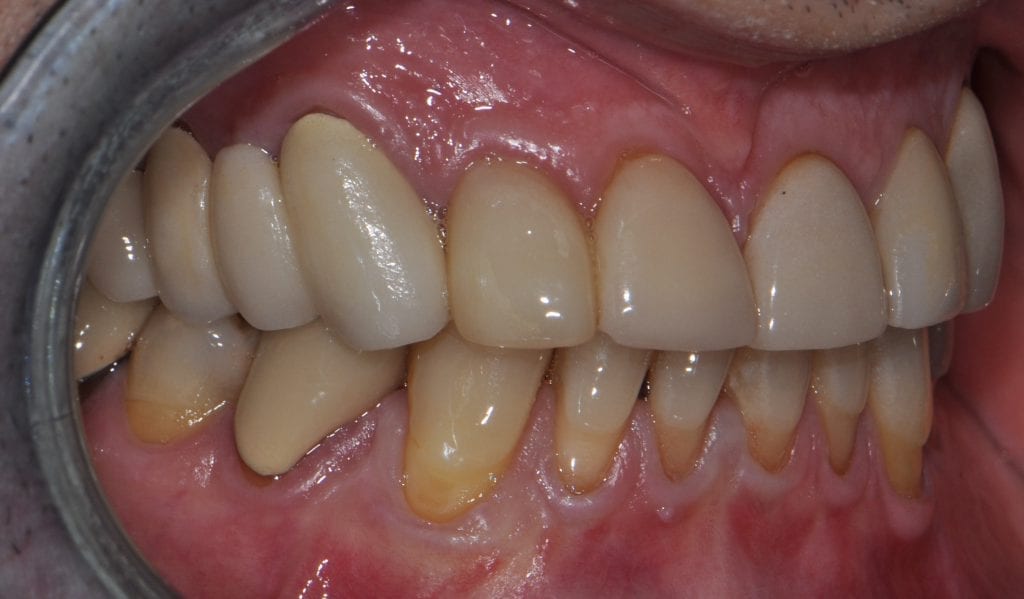

Pre-existing restorations that warranted replacement with an increase in vertical dimension.

Pre-existing restorations that warranted replacement with an increase in vertical dimension. The upper and lower arch were captured with the medit I500 and articulated together with enough clearance to accommodate new restorations and to restore the patient to an ideal tooth position.